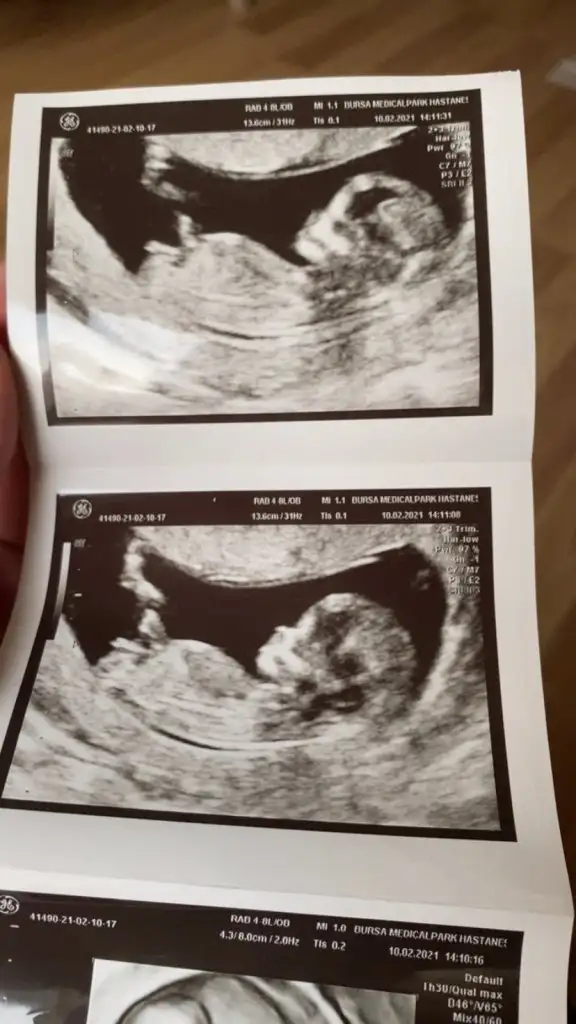

12+1iz :) bizede yorum yapan olur mu :)

31,6 KB · Görüntüleme: 211

Kiz erkek aslinda fark etmiyor ama yavrumu severken ona kizim ya da oglum demek icin merak ediyorum 🥰😘